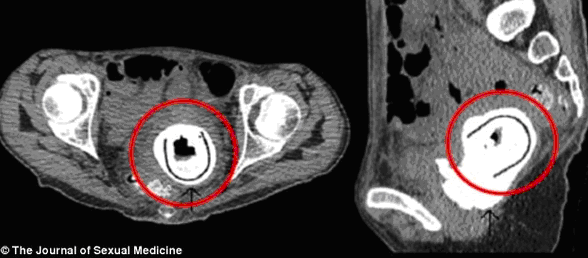

Bệnh viện Hoàng gia Aberdeen, Scotland đã tiếp nhận ca mắc kẹt dị vật trong cơ thể vô cùng hy hữu của một nữ bệnh nhân 38 tuổi. Một món đồ chơi tình dục có chiều dài tới 11 cm nằm trong âm đạo của cô suốt 10 năm mà cô không hề hay biết.

Chỉ sau khi xuất hiện những triệu chứng bao gồm sút cân nghiêm trọng, rùng mình hay hôn mê, người phụ nữ này mới tới bệnh viện khám. Các bác sĩ đã phát hiện và phẫu thuật lấy ra một món đồ chơi tình dục có chiều dài 11 cm từ âm đạo của cô.

Các bác sĩ cho biết, đây là trường hợp đầu tiên mà đồ chơi tình dục lại mắc kẹt trong âm đạo của phụ nữ trong khoảng thời gian dài tới như vậy.

Hình chụp X-quang âm đạo của người phụ nữ. |